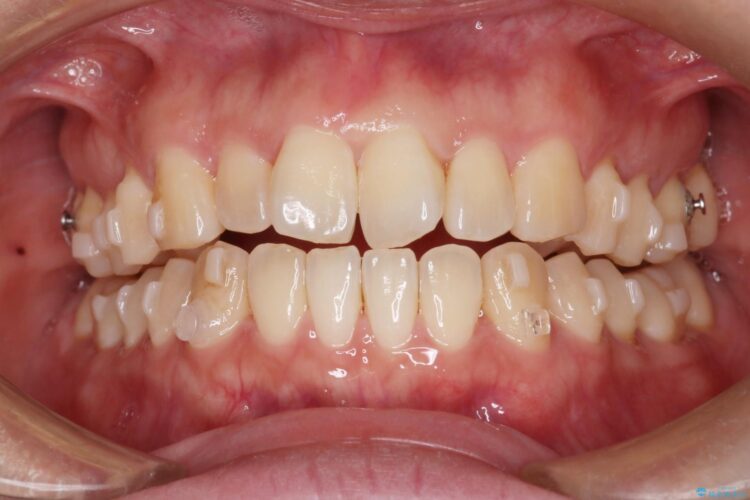

かみ合わせを整えるためにゴム掛けも併用して治療を行いました。

患者様にマウスピースの使用とゴム掛けを頑張っていただいたおかげでリファイメント(マウスピースの再発注)も1回で終了することができました。